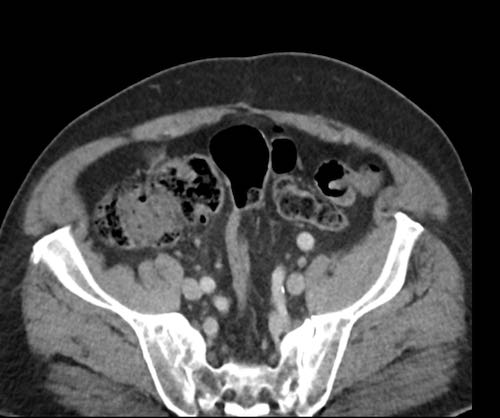

Ca lâm sàng 2

Cuộn qua các lát cắt.

Bạn có thể phát hiện tất cả các tổn thương cấy ghép phúc mạc không?

.jpeg)